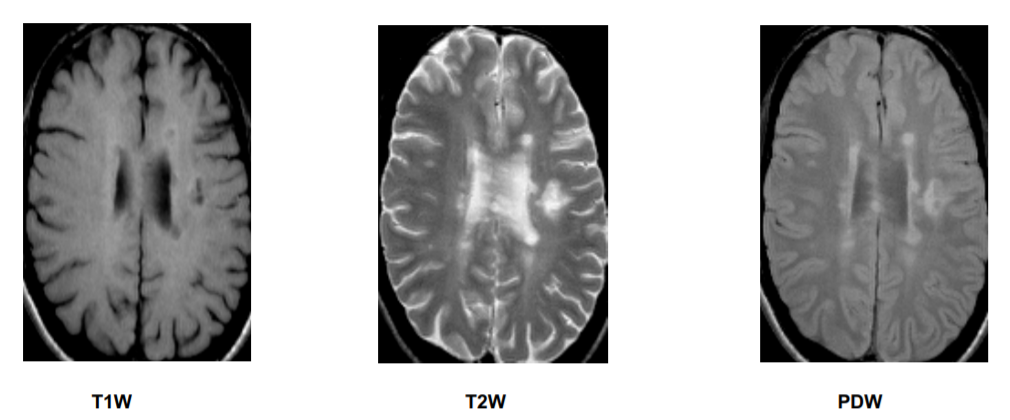

What features are bright and which are dark on a T1 weighted MRI image?

[IMPORTANT]

Bright on a T1 weighted image:

Dark on a T1 weighted image:

Which features are bright and which are dark on a T2 weighted MRI image?

Bright on T2 weighted image:

Dark on T2 weighted image:

What is the pathology shown in these images?

What is the best weighting to view MS lesions?

[EXTRA]